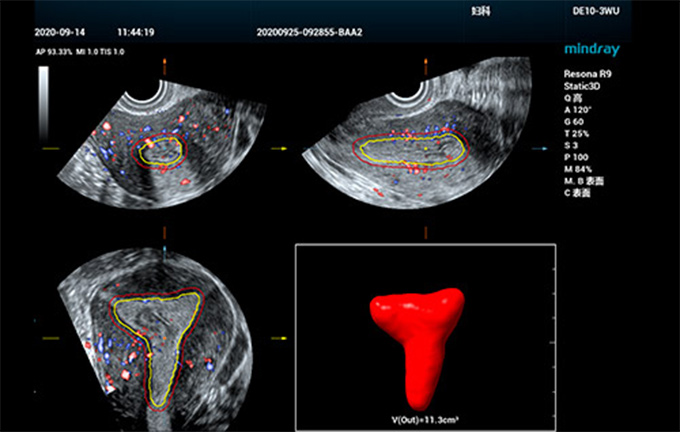

为提升妇产超声检查的效率与准确率,更好地实现生殖系统疾病和肿瘤的早发现,针对卵泡和子宫的超声检查,仁合提出了一系列智能化解决方案,助力医生进行高效临床诊断。比如,面向子宫应用场景,仁合推出了业内首款全自动子宫内膜容受度分析工具Smart ERA,即便针对不同类型的子宫内膜结构,也能够实现3D自动容积成像,并支持子宫内膜体积和厚度以及子宫内膜血流指数的自动测量。精简操作流程,极大地提升了检查一致性与诊断效率,让医生更自信、从容地应对孕前超声检查,如百步穿杨,既快且准。